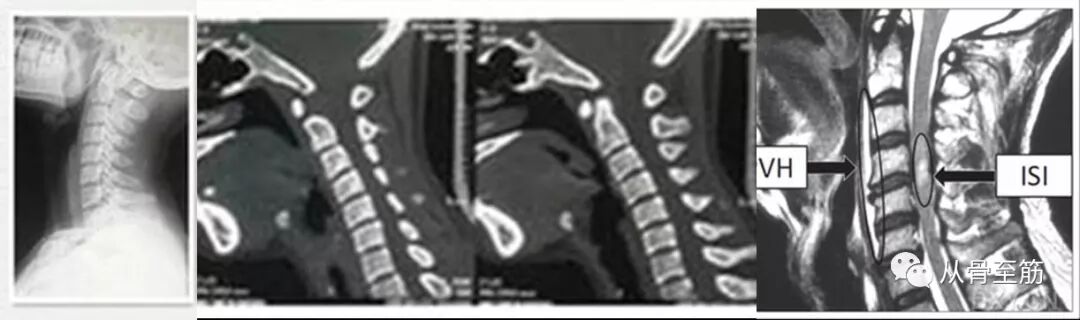

? ? ? ?无骨折脱位型颈脊髓损伤指在有先天性、发育性或退行性颈椎管狭窄、黄韧带肥厚或骨化、颈椎不稳、颈椎发育异常、急性颈椎问盘突出或脱出等病理基础上,因外伤导致四肢感觉、运动障碍,但颈椎x线片或CT检查并无颈椎骨折脱位的表现。有学者将其列为脊髓损伤的一种特殊类型。无骨折脱位型颈脊髓损伤机制一直存在争议,目前比较一致的观点是颈髓损伤在颈椎退变、椎管狭窄储备间隙明显减少的病理基础上发生,外力仅是造成损伤的诱发因素。根据外力形式,损伤机制可分为过伸损伤、屈曲损伤、纵形牵拉性损伤、缺血性损伤等。多见于颈椎存在异常的中老年人。外伤后引起的脊髓水肿、血肿也是脊髓损伤的重要因素。其中颈椎管狭窄和急性颈椎间盘突出或脱出是最主要的病理基础。当这些因素存在时,在外力的作用下可造成脊髓损伤。

诊断需行X线片检查、CT、MRI(核磁共振)等检查加专科医生查体诊断。